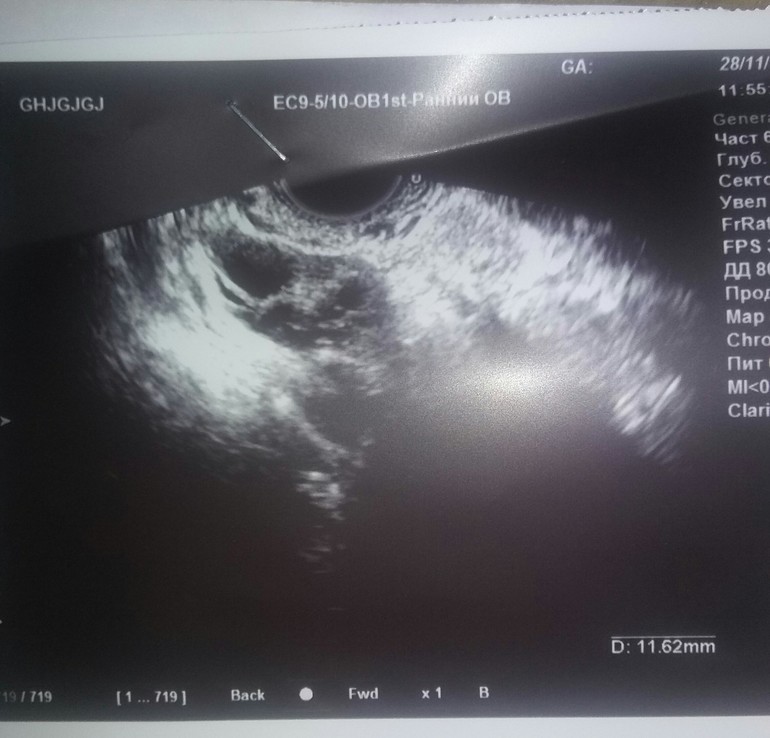

узи на 24 дц

ФолликулометрияДевочки доброе утро. Планируем с июля. Цикл обычно 31 день, все 3 месяца стабильно отслеживала овулю по тестам и базальной температурой. Все хорошо, разница 0,4 градуса. Тесты полосатились на 15-17 дц. В этом месяце бросила мерить базальную( оставила только тесты), и решила попить боровую матку. По ощущениям мне понравилась она. Нормализовался сон, перестала вставать в туалет по ночам, исчезли признаки ПМС. Но подозрительно перестала болеть грудь, и тест на овулю упорно отрицательный. Решила посмотреть по узи что же там твориться.. Была на узи на 24 дц. и вот результат. Посмотрите пожалуйста кто разбирается в узи. Я так понимаю травка сбила цикл. и у меня до сих пор длится первая фаза. Можно еще надеется на позднюю овуляцию или остается только ждать месячных? Заключение и фото прилагаю.